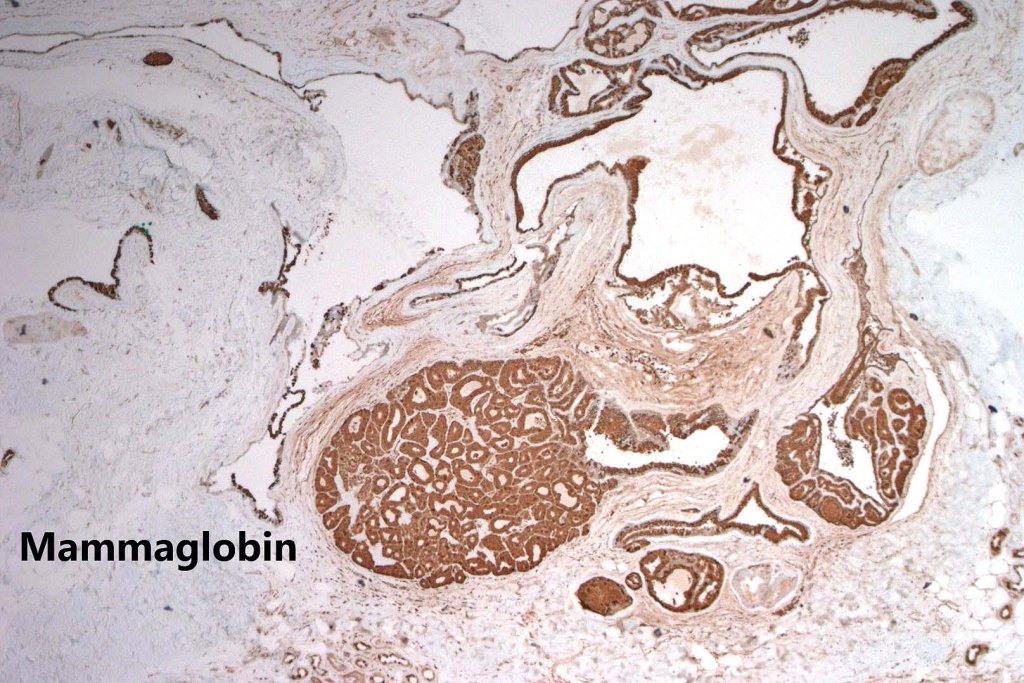

•CK7, CK18, GATA3, HMFG, GCDFP-15+ve

•Myoepithelial cells SMA, S100, p63 +ve